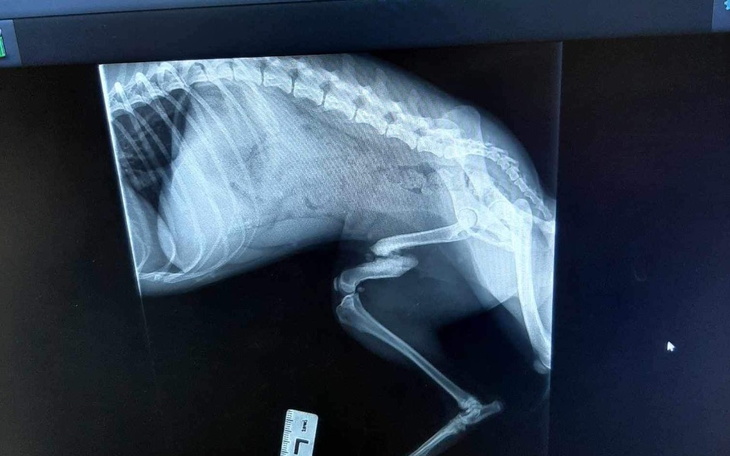

Czas przedstawić Fifi. Suczka bytowała na stacji cpn, najprawdopodobniej tam została potrącona. I tak ze złamaną nogą bytowała dalej na ulicy.Kiedy trafiła pod opiekę Piotra miała anaplazmoze - chorobę odkleszczową i na tym trzeba było początkowo się skupić.Kiedy trafiła do Zacisza nadal utykała. Zostały wykonane zdjęcia rtg i okazało się, że złamanie jest stare, częściowo zrośnięte, ale noga jest krótsza i może jej doskwierać przez resztę życia dlatego została podjęta decyzja o operacji.